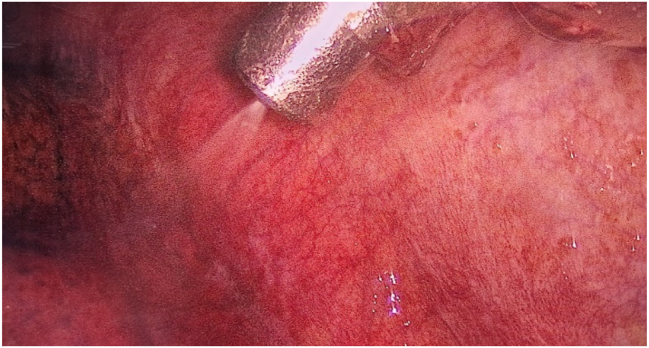

Methods: Patients eligible for PITAC and treated at Odense PIPAC Center were included. PITAC was performed in lateral decubitus or prone position under double-lumen endotracheal tube ventilation to allow exclusion of the lung if necessary. After positioning of the ultrasound-guided trocar, the second trocar is inserted by video-assisted thoracoscopy. MPE was evacuated and measured. Pleural lavage was performed if no or small amounts of MPE were present. MPE or pleural lavage fluid was analyzed cytologically. Visible PLM was biopsied and sent for histology assessment using a four-tiered Thoracic Regression Grading Score (TRGS). After a walkthrough of the safety checklist, the chemotherapy was nebulized followed by 30 min of passive diffusion. The chemotherapy and chemotherapy-saturated air was evacuated through a closed bag and ventilation system.